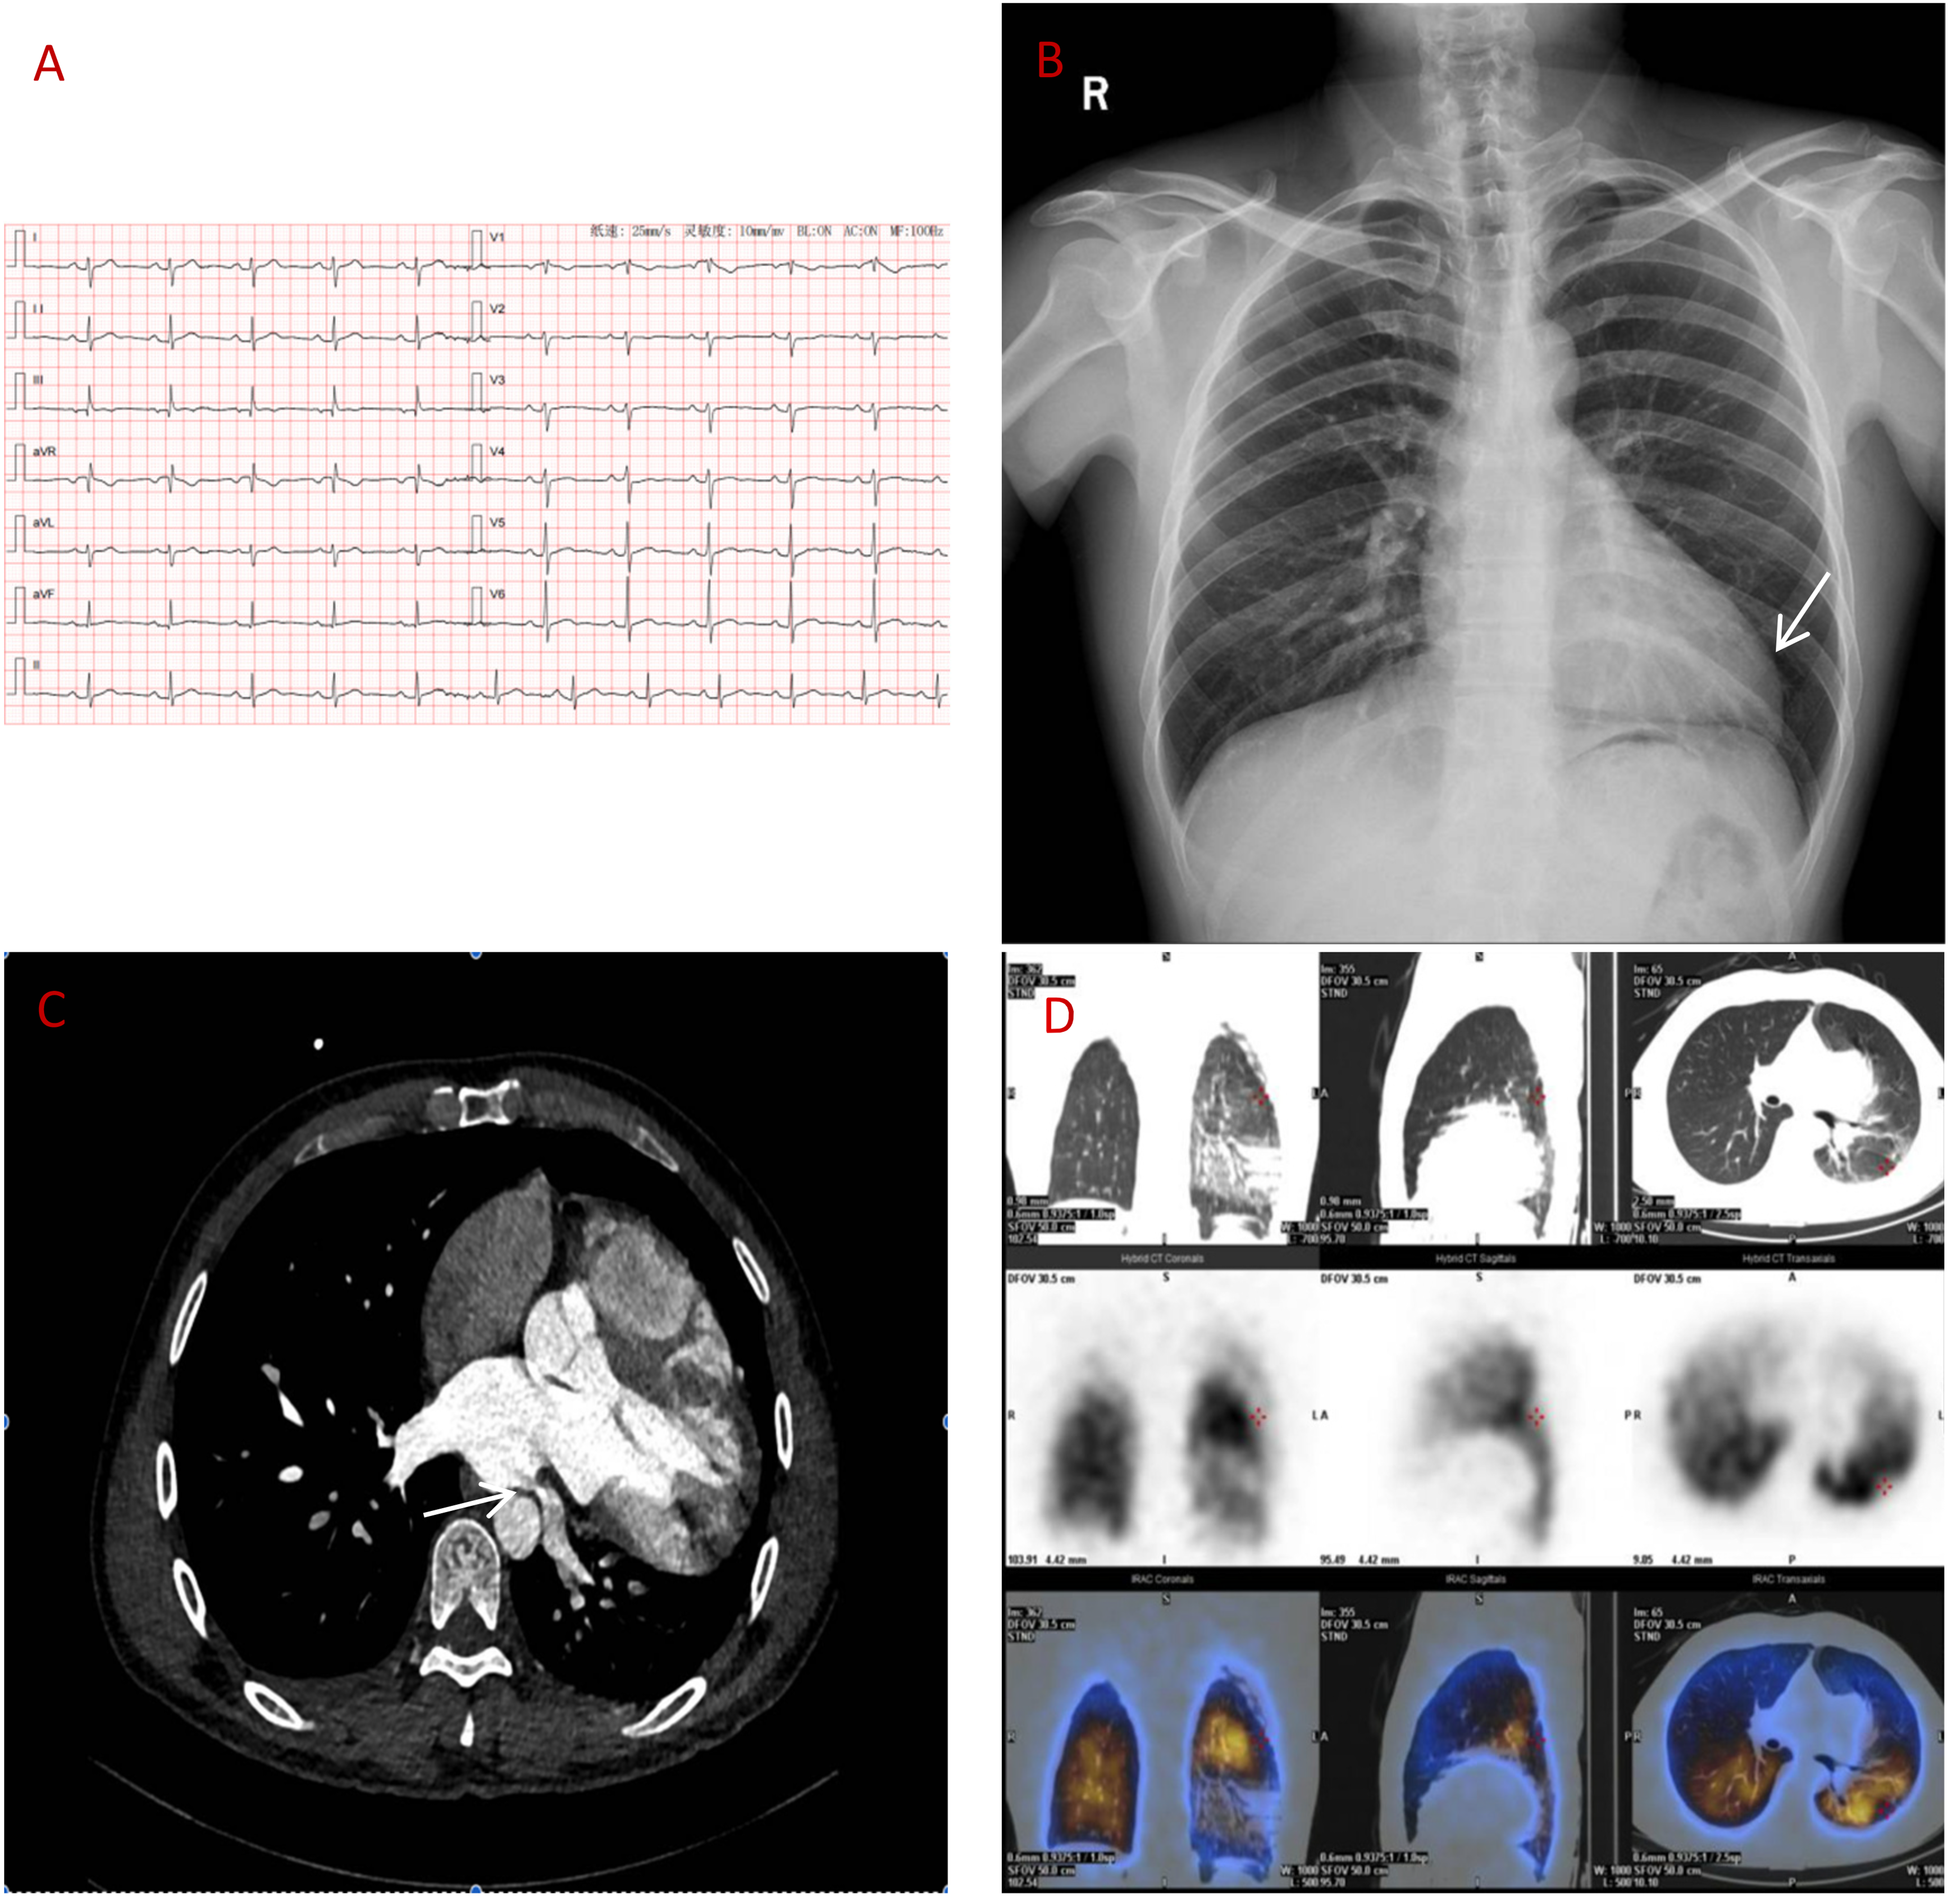

A 39-year-old man presented with two months of intermittent left-sided chest tightness (5-minute episodes, 2–3 times/month). Prior coronary angiography findings were normal, whereas CT pulmonary angiography findings suggested left lower lobar PE. Right heart catheterization revealed normal pulmonary pressure. Despite therapeutic rivaroxaban (15 mg twice daily) for 4 weeks, his symptoms intermittently persisted. Physical examination revealed a laterally displaced apical impulse (6th intercostal space, midclavicular line). Vital signs and laboratory results (NT-proBNP, CBC, and renal/hepatic function indicators) were unremarkable. Electrocardiography revealed sinus rhythm with incomplete right bundle branch block and T-wave abnormalities (Figure 1A). Echocardiography revealed right ventricular enlargement (52 mm; normal 20–42 mm) and mild mitral regurgitation. Chest x-ray revealed left ventricular elongation (“Snoopy sign”; Figure 1B).

Figure 1

(A) ECG: sinus rhythm, incomplete right bundle branch block. (B) Chest x-ray: elongated left ventricular contour. (C) CT angiography: left atrial compression of the left lower pulmonary vein (over 90%). (D) Lung perfusion scan: low perfusion in the left lower lobe.

Despite initial imaging suggesting PE, persistent symptoms and negative D-dimer levels contradict typical PE progression. Repeat CT angiography revealed right ventricular enlargement and mild left lower pulmonary vein narrowing (Figure 1C). A lung perfusion scan revealed a small wedge-shaped perfusion defect in the dorsal segment of the left lower lobe, suggesting pulmonary embolism (Figure 1D). Right heart catheterization revealed normal pulmonary artery pressure and vascular resistance. Pulmonary angiography revealed no filling defects or branch truncations in the right pulmonary artery (Pulmonary flow grade 3) or left pulmonary artery. However, delayed contrast flow in the left lower pulmonary artery and venous return (Pulmonary flow grade 2) provided insufficient evidence for pulmonary embolism (5). A multidisciplinary team review revealed leftward cardiac rotation, discontinuity of the left pericardium (Figure 2), and left atrial compression of the lower pulmonary vein, which were consistent with CAP. Given the mild symptoms and low degree of herniation risk, conservative management with follow-up was chosen. At 3-month follow-up (July 2025), the patient remains asymptomatic. This case uniquely highlights pulmonary venous compression due to cardiac displacement-a previously unreported manifestation of CAP-suggesting its clinical variability.